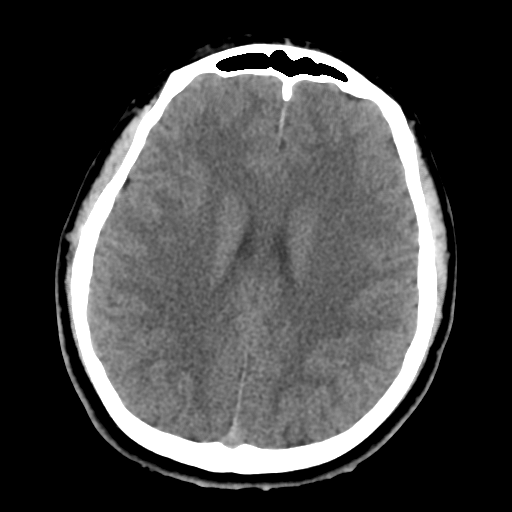

16살 환자의 brain CT를 보도록 하자.

어린 나이라 나이든 사람의 brain CT보다 뇌 실질 자체의 부피가 크고 빈 공간이 적어 보이게 된다.

사람의 두개골 내에는 대뇌와 소뇌, 그리고 좌우 반구를 나누는 얇고 넓은 막이 있다. 좌우 대뇌를 나누는 구조물을 falx cerebri 라고 하며, 대뇌와 소뇌를 나누는 구조물을 tentorium cerebelli라고 한다.

위에 16살 환자의 경우 대뇌와 소뇌를 나누는 격벽 구조를 따라 뇌출혈이 발생한 경우이다.

다행히 예후가 나쁘지는 않지만, 출혈량이 늘어나는지 확인할 필요는 있기에 입원이나 단기간 외래 추적관찰이 반드시 요구되는 상황이다.